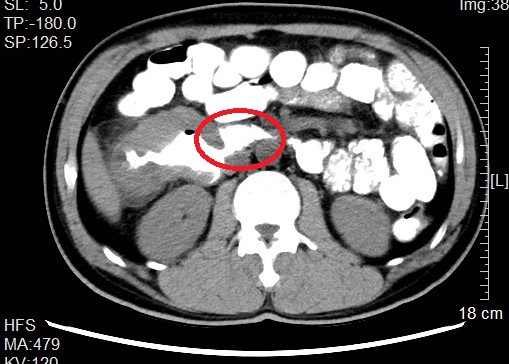

来自省内正值中年的邹先生和张先生都因“阵发性腹痛不适感”就医而发现结肠肿瘤,慕名转诊找到我院治疗。杨春康教授接诊,经过详细全面的检查后,发现二者的病情相似,都为升结肠近肝曲部的肿瘤且肿瘤已侵犯临近的重要脏器——十二指肠,全身其他部位没有发现肿瘤转移病灶,属于局部晚期病例。面对仍有治愈希望的病人以及家属的殷切希望,尽管病情高度复杂,手术风险和压力巨大,杨春康教授和他率领的医疗护理团队没有在困难面前退缩。在与病人及家属充分沟通后,决定为他们手术,并制定周密的手术方案。

虽然已有过多例成功案例在先,但面对此高难度手术,杨春康教授始终严阵以待,在总结前期手术经验基础上,与麻醉科、手术室护理团队等做好充分的术前准备,在团队成员的密切配合下,历时5小时余,顺利完整切除肿瘤,成功完成手术,术中出血近约300ml。